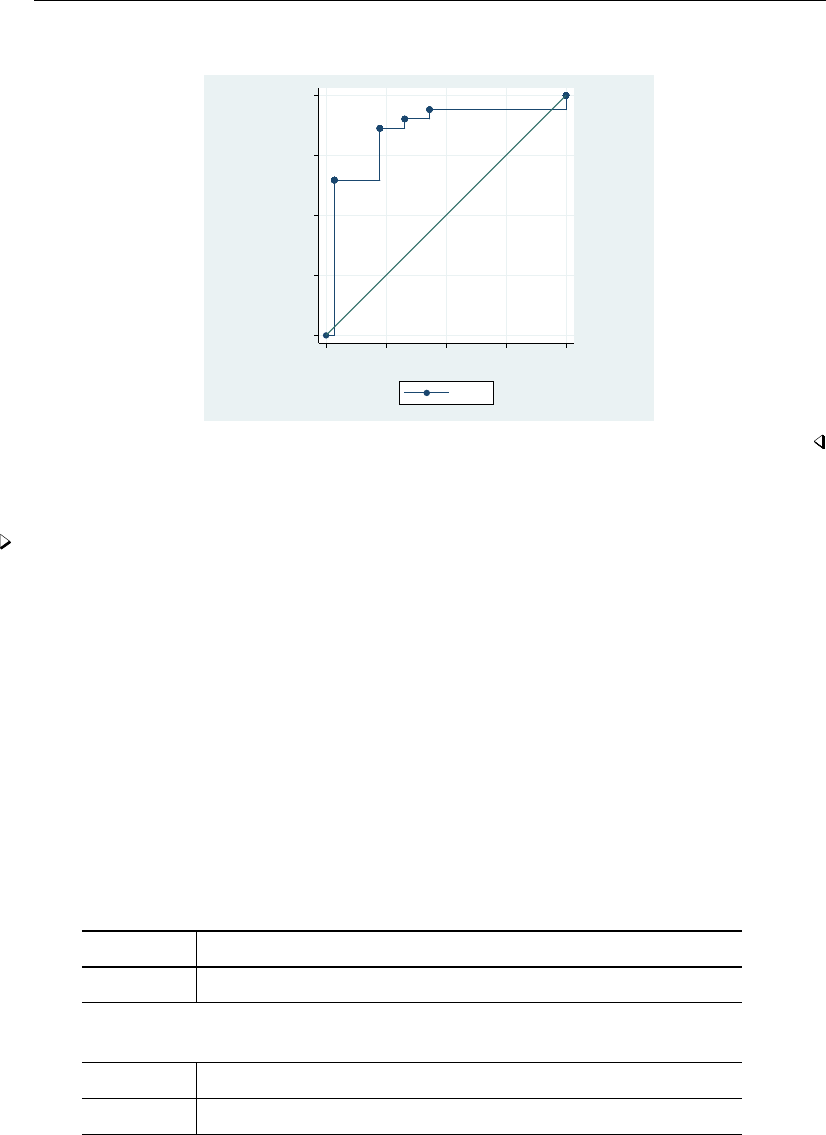

- roc

- roccomp

- rocfit

- rocfit postestimation

- rocreg

- rocreg postestimation

- rocregplot

- roctab